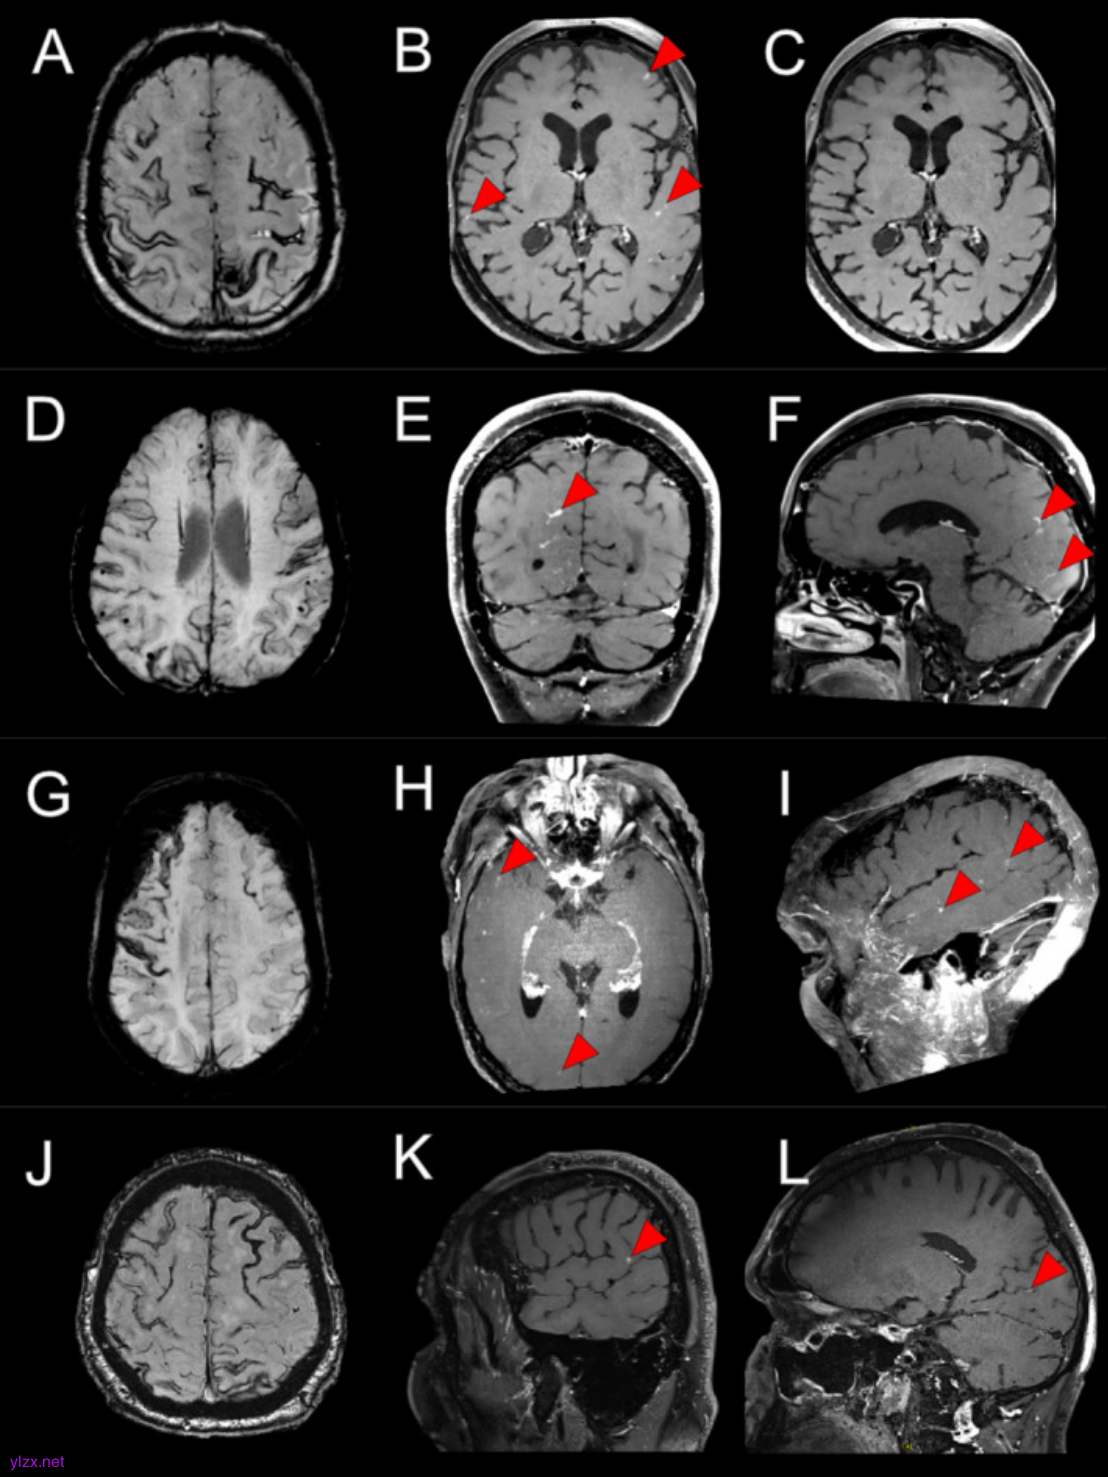

图2.每行包含案例 5 和 6 的磁共振成像

使用 VWI 的高分辨率造影剂后 MRI,在 6 名持续性 CAA 相关 TFNE 患者中描述了软脑膜、实质和小皮质动脉壁增强的各种组合,与短暂性炎症一致。在 6 例病例中的 5 例中,增强包括与解剖学上与 TFNE 症状相关的区域,尽管增强通常相当弥漫,以后(顶枕)为主。这些观察结果表明,炎症可能在持续性 CAA 相关 TFNE 的病理生理学中发挥作用,并且可能在更普遍的 CAA 中发挥作用。

钆造影剂后脑部 MRI 和高分辨率血管壁成像 (vessel wall imaging,VWI) 提供了一种非侵入性方法来评估单个小血管内的血脑屏障 (blood–brain barrier,BBB) 破坏和血管病变变化。1月8日,伦敦大学 David J Werring教授团队在Annals of Neurology(IF=8.1)在线发表了题为“Inflammation in Cerebral Amyloid Angiopathy-Related Transient Focal Neurological Episodes”的研究,描述了 6 名持续性 CAA 相关 TFNE 患者,其中钆后 MRI 发现与小血管、软脑膜和脑实质急性炎症一致的异常。

在本研究中,2 例患者接受了大剂量皮质类固醇治疗,异常增强和 TFNE 症状消退,与先前的病例报告一致,该患者与软脑膜动脉和沟静脉血管壁增强相关,皮质类固醇治疗后有所改善。然而,另一名患者在未经治疗的情况下表现出放射学改善,因此这些观察结果是否表明治疗效果或自发改善仍不确定。值得注意的是,发现了新的增强区域,以及在先前受增强影响的区域之外的区域出现新的小 DWI 病变,这表明存在动态和广泛的疾病过程。需要进一步的研究来确定炎症是否可能是散发性 CAA 中常见的解剖学分散的小皮质和皮质皮质下 DWI 病变的触发因素。